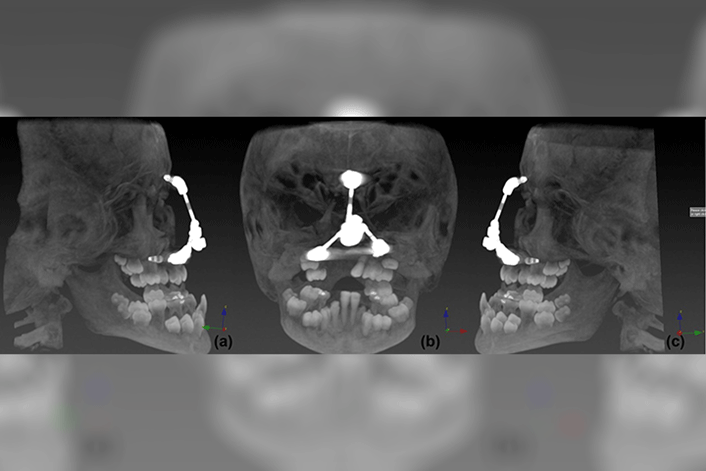

Two titanium implants were surgically implanted; one was placed in the glabella region and one was placed in the left paranasal region. After osseointegration, a third implant was placed in the right paranasal area to form a tripod form of retention for the future prosthesis.

This report describes the complete treatment plan which required a multidisciplinary team to construct a rigid implant-retained framework capable of both magnetic retention of the removable nasal prosthesis and expansion to accommodate the future cranial facial growth of the patient.